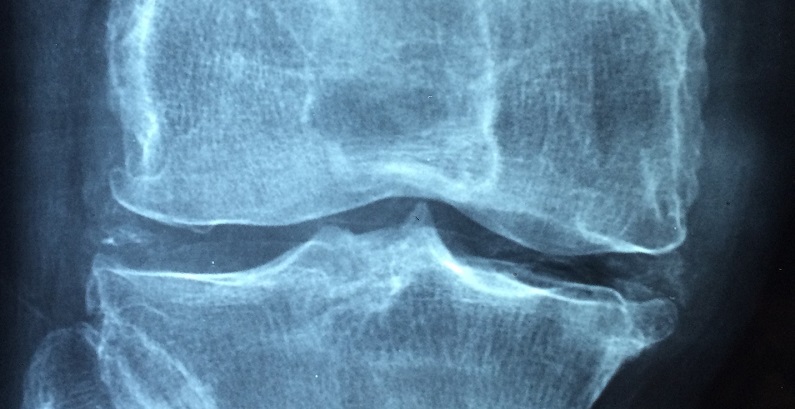

Alcuni sintomi dell’osteoartrosi del ginocchio potrebbero essere trattati con lo zenzero nero tailandese

Le persone che soffrono di osteoporosi al ginocchio (un semplice deterioramento della cartilagine) potrebbero trovare una soluzione nello zenzero nero thailandese (Kaempferia parviflora). Secondo uno studio pubblicato sul Journal of Natural Medicine, infatti, potrebbe essere utilizzato per ridurre efficacemente i sintomi.

Gli studiosi hanno esaminato l’effetto dell’estratto di zenzero nero tailandese sui topi con osteoartrite al ginocchio. I risultati hanno rivelato che l’estratto di zenzero tailandese nero riduceva il dolore e la gravità delle lesioni della cartilagine osteoartritica.

Inoltre, l’estratto di zenzero nero tailandese e i suoi componenti attivi, in particolare 5,7-dimetossiflavone e 5,7,4? -Trimetossiflavone, riducevano le metalloproteinasi della matrice di espressione (MMP). Le MMP sono i principali enzimi della matrice extracellulare, responsabili della degradazione del collagene all’interno della cartilagine.

Sulla base dei risultati emersi, i ricercatori hanno concluso che lo zenzero nero tailandese potrebbe alleviare gli effetti dell’osteoartrosi al ginocchio in maniera particolarmente efficace, non solo diminuendo il dolore, come potrebbe fare lo zenzero “normale”, ma intervenendo anche sulla produzione di collagene.